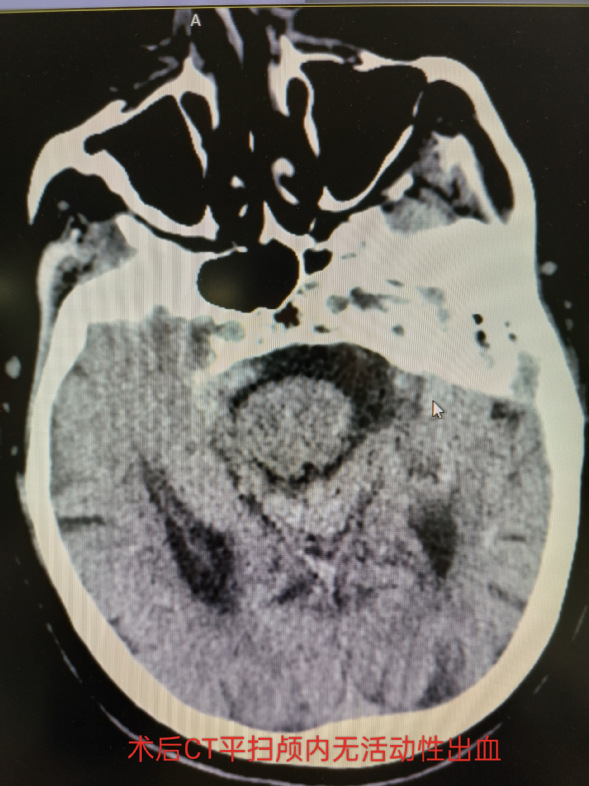

术前术后头部CT平扫

患者术后疼痛消失,成功治愈。